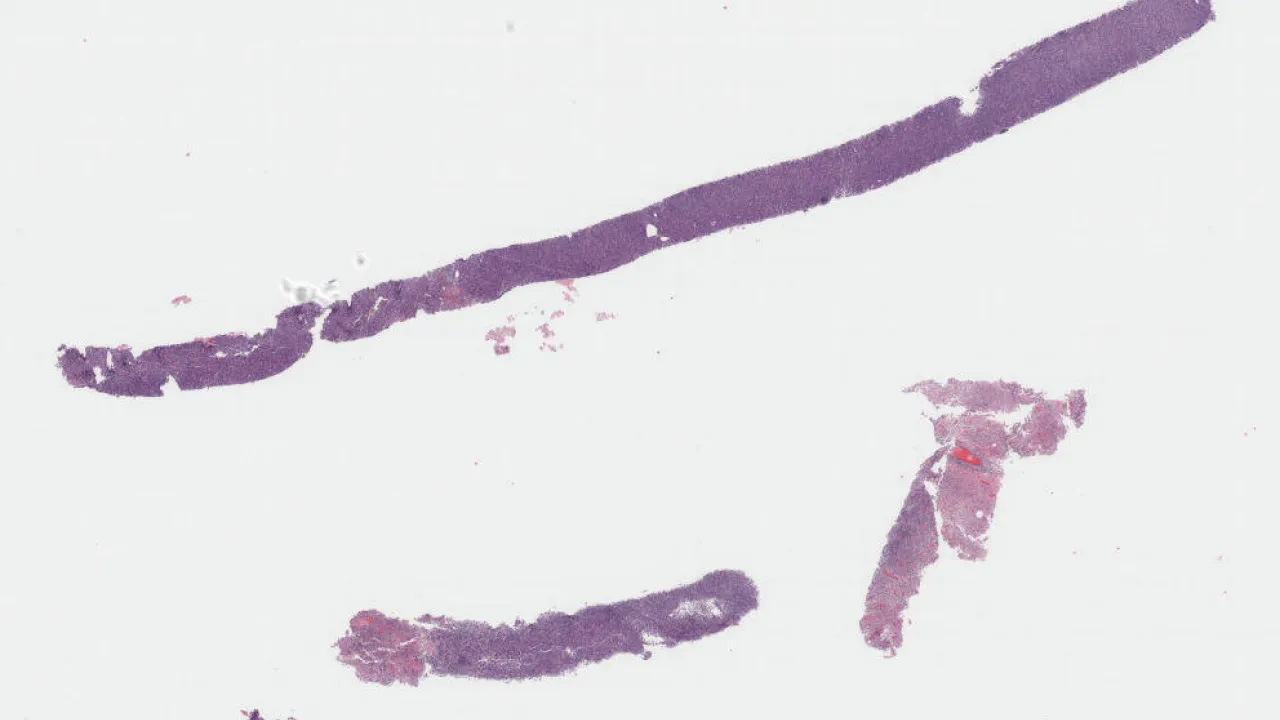

Sacrum, OEIS Complex